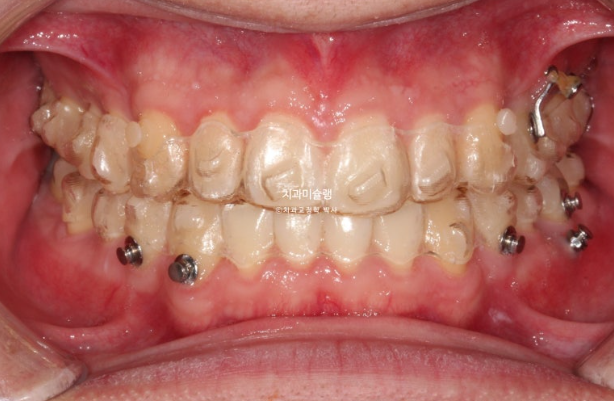

24.11

위 아래 중심선은 정확히 맞고

어금니 교합관계도 1급 입니다.

모든게 좋지만 환자분의 요구사항도 있었고 완성도를 위해 재제작을 1회 더했습니다.

11개 추가장치를 모두 낀 후 25년 6월 치료를 마무리 합니다.

이제 왜소치 무삭제 라미네이트가 들어갈 차례 입니다.

총 치료기간은 2년 6개월 재제작은 2회 했습니다.

어금니 교합은 좋고 1급 교합관계를 보입니다.